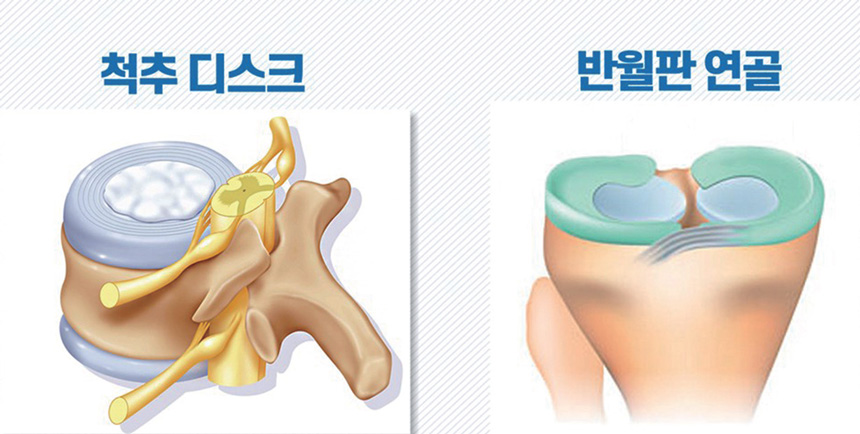

- 척추와 무릎 관절